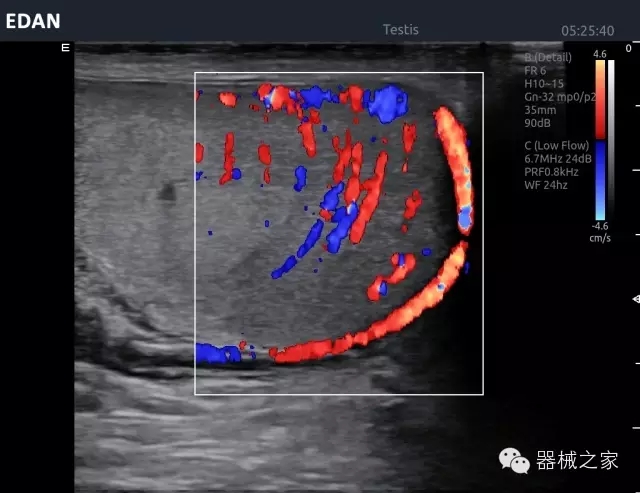

睪丸低速血流